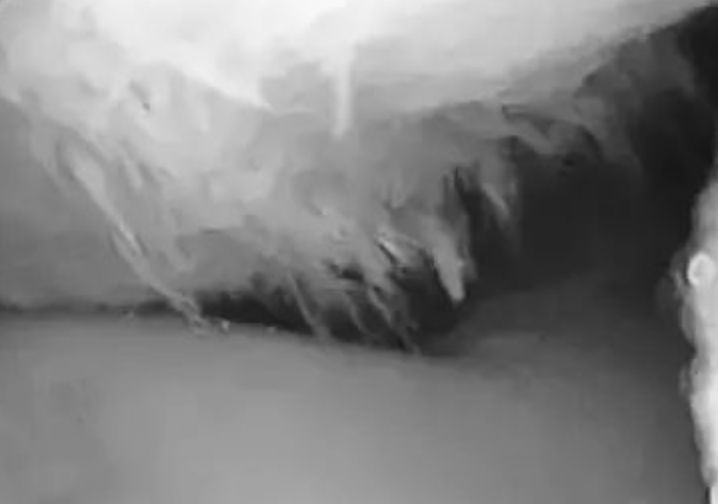

和“打软腿”相比,更严重的还是和膝关节其他部位发生不必要的接触和摩擦,关节受力也大大增加,长此以往,髌骨内侧就会磨损,这个过程被称为「髌骨软化」。表现为膝关节中心间歇性疼痛,下蹲和屈膝时会加重。单纯靠检查是很难区分出髌骨问题还是其他部位的问题,为了确诊,MRI是个直观的方法。

通过MRI可以进一步观察膝关节软组织的炎症和肿胀程度,结合关节检查,可以更系统地了解到膝关节活动功能的异常在膝关节侧面的MRI片中,可以看到髌骨朝向膝关节的内侧表面软骨边缘有些毛糙,表示已经发生了一定程度的破坏,这些破坏来自于关节软骨之间的磨损,损伤严重的情况下还可以看到附近少量的关节积液。

髌骨软化实际上是关节面毛糙